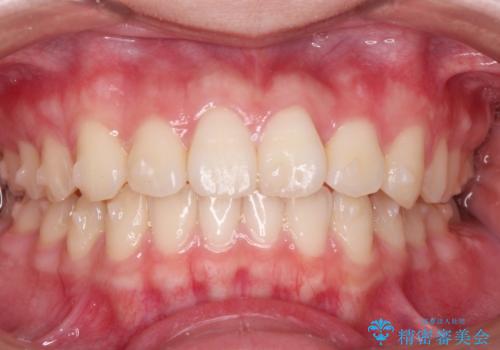

前歯のねじれをマウスピース矯正で治したい

- 前歯のねじれや がたつきを治したい、マウスピース矯正治療を希望され来院されました。

初診時程度のがたつきやねじれであれば、26枚以下のマウスピース矯正 モデレートプランで、比較的リーズナブルに矯正治療を受けていただくことができます。

実際の治療期間は約半年で仕上がりのような綺麗な歯並びを手に入れることができました。